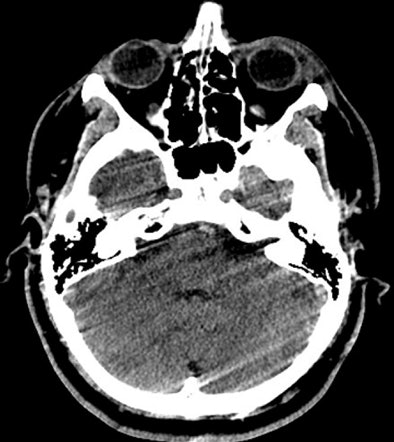

![]() |

| Presented with the exact same images as radiologists and blinded to diagnosis, context, or history, technologists wanted to repeat almost 30% more than the average radiologist or fellow. |